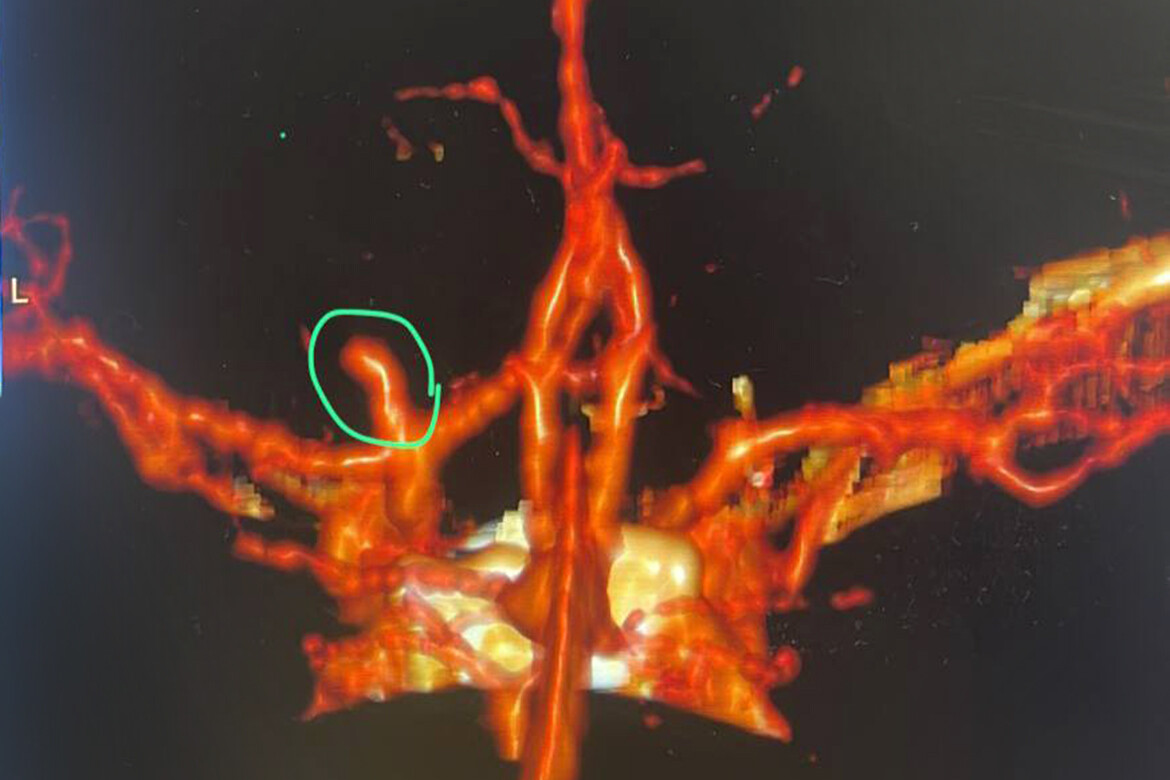

У Динара разорвалась аневризма левой среднемозговой артерии, которая была у него предположительно с рождения. Из-за разрыва аневризмы случился геморрагический инсульт.

Аневризма была 5 мм в диаметре. Это, объясняет хирург, достаточно крупная аневризма для ребенка и средняя для взрослого. На место аневризмы ангиохирурги поставили специальную платиновую спираль, которая перекрывает доступ крови к ней. При таком методе лечения с течением времени аневризма полностью зарастет.